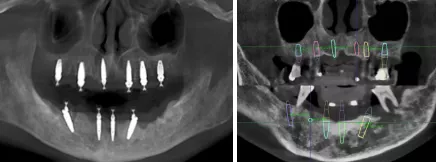

- 11、23、32、42植入ø3.3*12mm NC Straumann BLT种植体 4颗

- 14、24植入ø4.1*10mm RC Straumann BLT种植体2颗

- 16、26植入ø4.1*8mm RC Straumann BLT种植体2颗

- 35、45植入ø4.1*12mm RC Straumann BLT种植体2颗

- 术后拍摄CBCT,使用士卓曼CoDiagnostix导板软件内的种植位点评估功能进行术后与术前设计对比,误差较小。